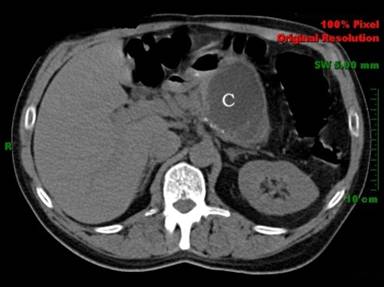

A fifty-two-year-old male presented with a 2-year history of epigastric abdominal pain radiating to his back with associated nausea and varying lengths of time. He had presented with similar symptoms to the emergency room one month prior, had abdominal imaging showing a lobulated cystic lesion in the tail of the pancreas, and was asked to follow up with his gastroenterologist. His past medical history was significant for alcohol and intravenous drug abuse, chronic pancreatitis, hepatitis C, uncontrolled diabetes, family history of pancreatic neoplasm, and personal history of MCN of the pancreas twelve years prior status post distal pancreatectomy and splenectomy. He has been seen in and out of the hospital for pancreatitis likely secondary to alcohol use and possibly triglycerides due to uncontrolled diabetes. On physical exam his vital signs were normal and he had epigastric tenderness. His amylase and lipase at the time of evaluation were normal. Contrast-enhanced computed tomography (CT) scan of abdomen/pelvis showed a lobulated cystic lesion in the distal pancreatic body measuring 4.5x6.5x5.8 cm (Figure 1). Endoscopic ultrasound (EUS) with fine-needle aspiration (FNA) showed a 7.5x5.1 cm septated cyst in the body of the pancreas with irregular walls and mural nodules shown within the cyst (Figure 2). Of note, there were at least 2 mural nodules within the cyst on EUS with the largest measuring 13x9.8 mm. Cyst fluid analysis showed an amylase level of 331 U/L and a CEA of 68.5 ng/mL.

Figure 1. CT scan of the abdomen/pelvis showing a lobulated cystic lesion (C) that is 4.5x6.5x5.8 cm. |